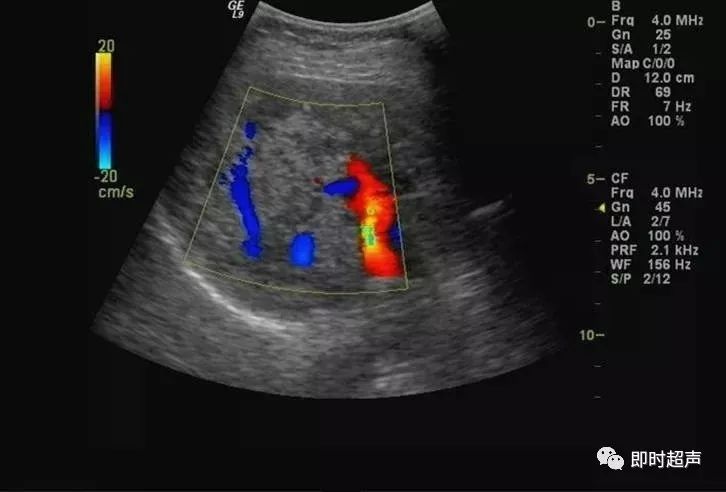

非均匀性脂肪肝:脂肪肝形成和发展过程中,受到门静脉血流中胰岛素和胰高血糖素含量以及肝内门静脉-体腔静脉交通支等因素的影响,脂肪浸润可表现为非均匀性。

依据超声表现可分为四型:

1、局灶浸润型:呈局灶性强回声,无包膜,边界不清,后方可伴衰减。

此型需与肝转移癌及肝血管瘤鉴别。

2、多灶浸润型:在回声相对正常的肝内,可见多发强回声。

3、叶段浸润型:一部分区域为低回声,其它区域为强回声。

此型需与肝转移癌鉴别,此型肝内血管走行正常,无靶环征及牛眼征。

4、正常肝残留型:肝脏弥漫性回声增强,其内可见低回声区,为轻度脂肪浸润或性对正常肝残留区,好发于胆囊床、门静脉主干周围。